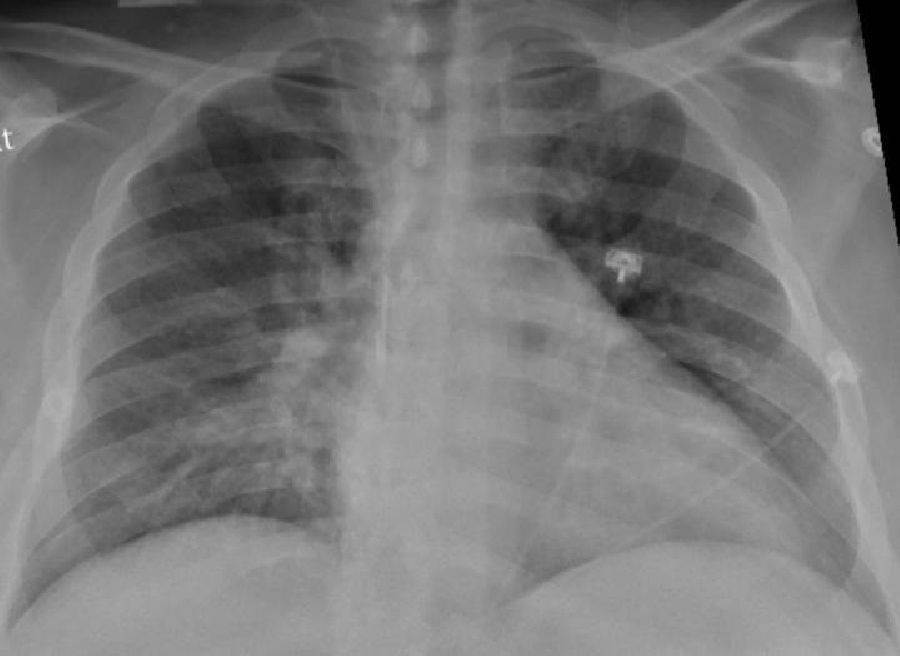

Un nuevo estudio del Colegio de Médicos y Cirujanos Vagelos de la Universidad de Columbia y del Centro Oncológico Integral Herbert Irving (Estados Unidos) ha dibujado la imagen más detallada hasta ahora de la infección por SARS-CoV-2 en el pulmón, revelando los mecanismos que dan lugar a la COVID-19 letal, y puede explicar las complicaciones a largo plazo y mostrar cómo la COVID-19 difiere de otras enfermedades infecciosas.

Publicado en la revista \'Nature\', el estudio descubrió que, en los pacientes que murieron a causa de la infección, la COVID-19 desencadenó una trifecta perjudicial de inflamación desbocada, destrucción directa y regeneración alterada de las células pulmonares que intervienen en el intercambio de gases, y cicatrización pulmonar acelerada.

Este nuevo estudio es único con respecto a otras investigaciones, ya que examina directamente el tejido pulmonar (en lugar de esputo o lavados bronquiales) utilizando perfiles moleculares unicelulares que pueden identificar cada célula en una muestra de tejido y registrar la actividad de cada célula, lo que da lugar a un atlas de células en el pulmón tras la COVID-19.